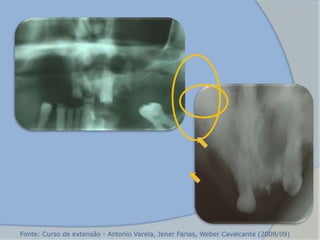

Fonte: Curso de extensão - Antonio Varela, Jener Farias, Weber Cavalcante (2008/09)

 Forma-se no interior do alvéolo

 Radio transparência de forma circular a oval

2. Cisto Periapical

Residual

(CASTRO et al, 2008)